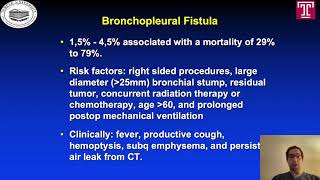

Concern for dehiscence of bronchial suture post pneumonectomy Delayed Bronchial Dehiscence - BPF Post Pneumonectomy - Bronchoscopy Closure

Delayed Bronchial Dehiscence - BPF Post Pneumonectomy - Bronchoscopy Closure Overholt bronchial stump closure after right pneumonectomy

Overholt bronchial stump closure after right pneumonectomy Infamous but Attractive: Transsternal Transpericardial Closure of Postpneumonectomy BPF

Concern for dehiscence of bronchial suture post pneumonectomy Delayed Bronchial Dehiscence - BPF Post Pneumonectomy - Bronchoscopy Closure

Delayed Bronchial Dehiscence - BPF Post Pneumonectomy - Bronchoscopy Closure Overholt bronchial stump closure after right pneumonectomy

Overholt bronchial stump closure after right pneumonectomy Infamous but Attractive: Transsternal Transpericardial Closure of Postpneumonectomy BPF